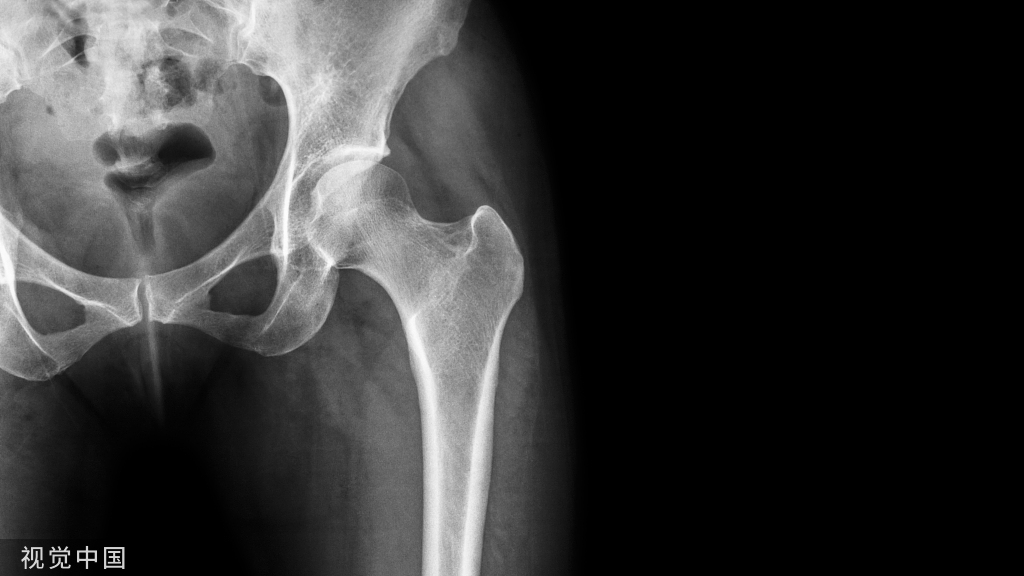

病例2:一位60岁女性主诉右髋部疼痛和外展肌无力,在初次右全髋关节置换术后出现大转子骨折。2/5 外展肌肌力。

(A-C)术前X光显示大转子有轻微骨折,和先前植入的右全髋关节假体,包括非骨水泥的股骨柄和非骨水泥的髋臼假体。(D和E)在外展肌重建前进行的MRI图像显示臀中肌腱仍然附着在大转子骨折片段上。这块骨折碎片已经移位,近端移位。臀小肌腱终止于股骨近端的软组织。外展肌重建术后18个月的报告包括:休息疼痛,3/10;行走疼痛,8/10;Harris髋关节评分,26;牛津髋关节评分,37。患者报告中度跛行,行走时使用助行器。